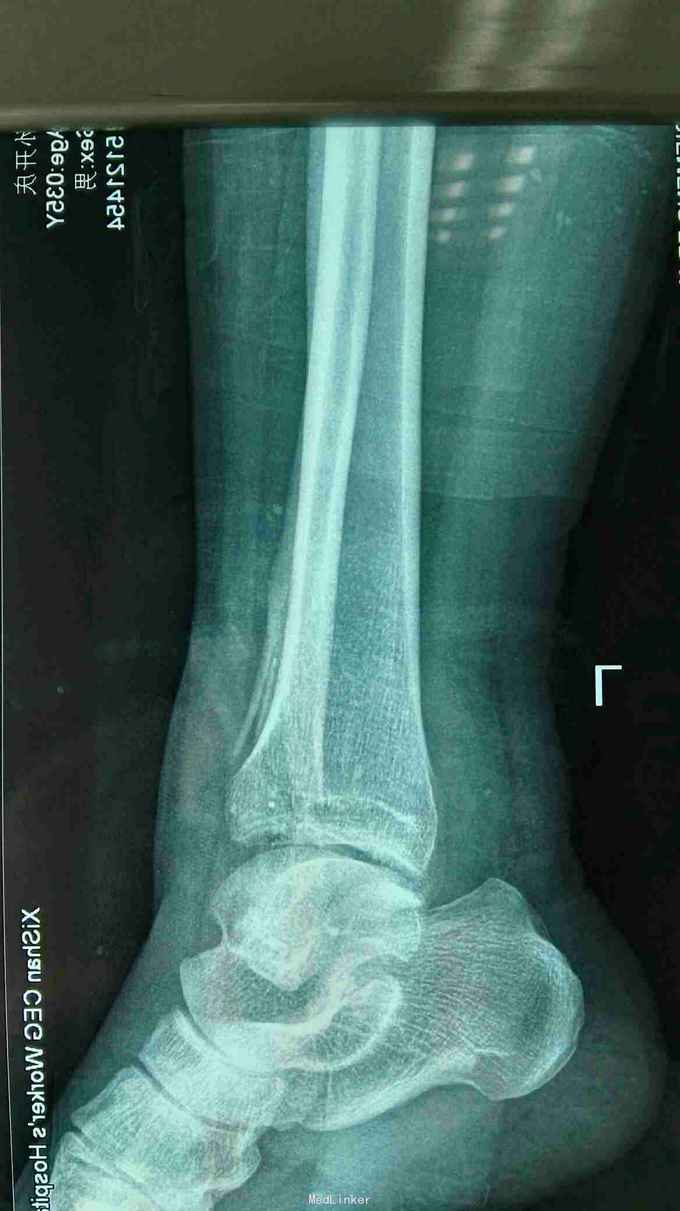

外踝毁损伤

患者男子,车祸致全身多次骨折,目前患者左外踝毁损伤,皮肤缺损约15*8cm,左外踝缺损长度5cm,目前一期手术给予清创+vsd负压吸引,给予局部冲洗。目前患者受伤第三天。术中情况见图。

左外踝入院时出院不止,伤口污染严重,血象高,d二聚体4500肝,肾功能正常

左外踝毁损伤